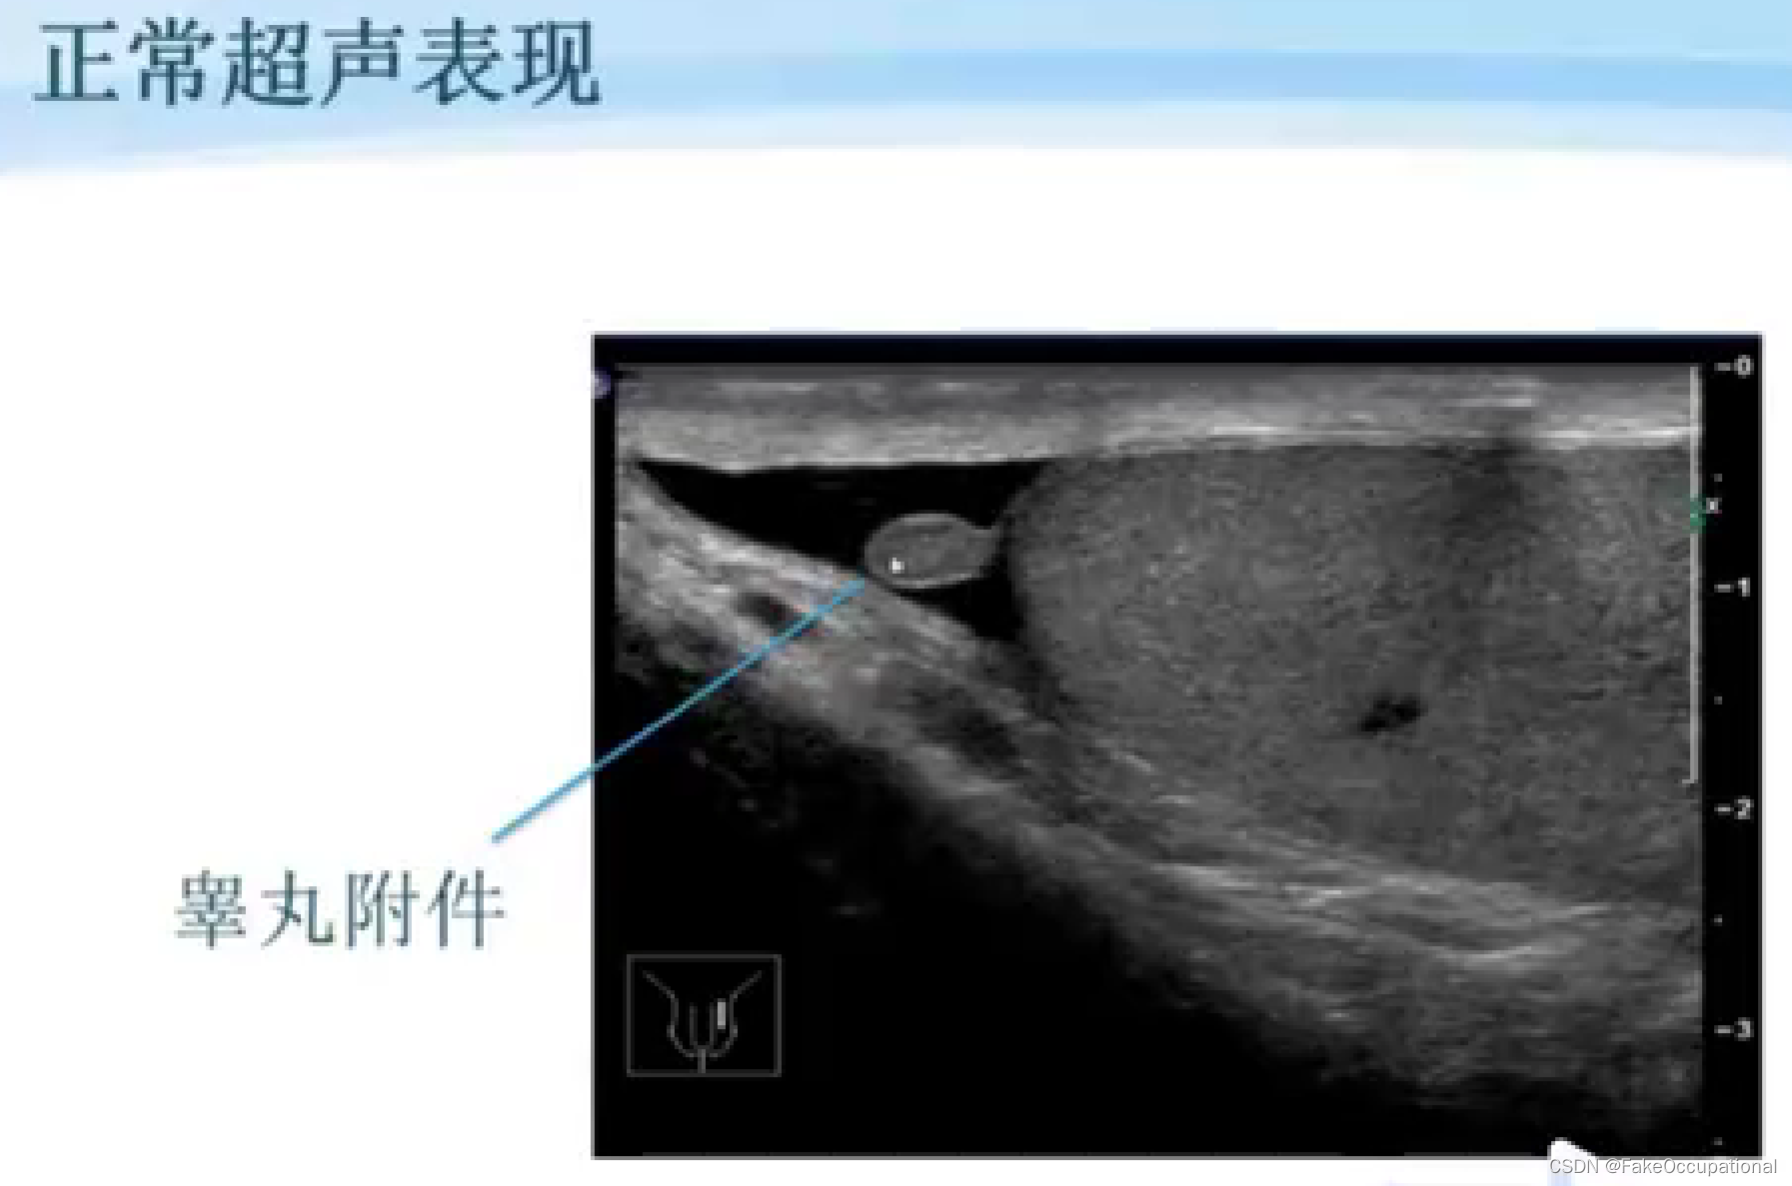

阴囊超声(和谐)